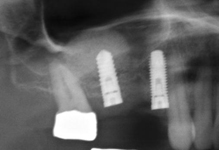

- Uzavřený, interní, vnitřní, crestální sinus lift

- Otevřený, externí, vnější, laterální sinus lift

LAS Kit

Souprava pro laterální přístup k sinus liftu, speciálně navržena pro bezpečný a méně invazivní laterální přístup k nadzdvihnutí membrány sinu. LAS Kit nabízí v závislosti na anatomii dutiny ústní a plánech operace různé využití.

CAS Kit

Souprava pro krestální přístup k operaci sinus liftu tím, že se vytvoří v kosti kónický odštěpek, kterým lze membránu bezpečně nadzvednout.